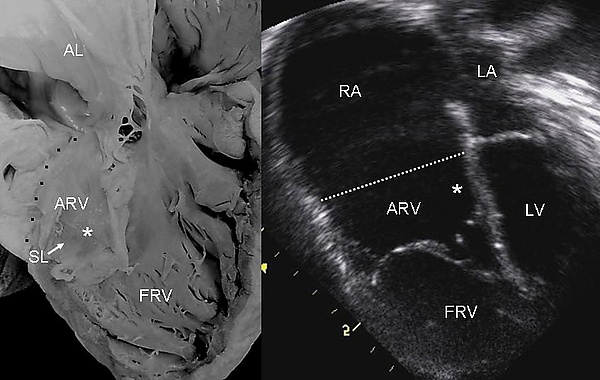

При этом пороке сердца створки правого атриовентрикулярного клапана исходят из стенок правого желудочка, а не из предсердно-желудочкового кольца и неполностью смыкаются (недостаточность трёхстворчатого клапана). Таким образом, полость правого желудочка оказывается уменьшённой по сравнению с нормой, а часть правого желудочка от предсердно-желудочкового кольца (где клапан должен был находиться в норме) до смещённого вниз трёхстворчатого клапана становится продолжением правого предсердия. Также при аномалии наблюдается незаращение овального отверстия (между правым и левым предсердиями). Из-за таких анатомических изменений аномалия Эбштейна характеризуется:

- Уменьшением полости правого желудочка. Правое предсердие увеличивается в размерах и расширяется. Часть венозной крови перетекает в левое предсердие через открытое овальное отверстие и смешивается с артериальной. Это приводит к уменьшению содержания кислорода в артериальной крови и гипоксии органов и тканей. Возможны нарушения ритма сердца.

Эхокардиографическое исследование. Отмечаются деформация эхосигнала от створок и объёмное увеличение размеров правого предсердия.